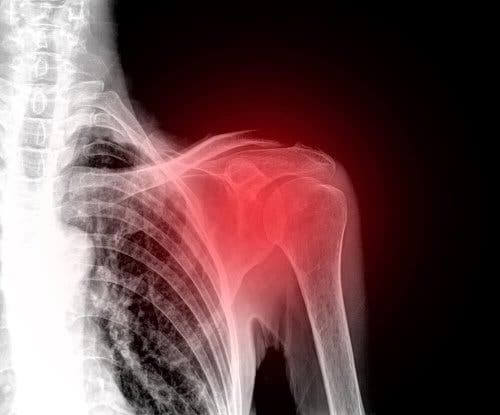

En rotator cuff læsion er en skade, der ofte rammer middelaldrende skuldre. Således er det i øjeblikket en af de førende årsager til skuldersmerter.

Rotator cuff er en gruppe muskler og sener, der forankres i skulderbenene. De er ansvarlige for at holde dette led stabilt og i stand til at udføre alle bevægelser korrekt.

Desværre er skulderen en del af kroppen, der har tendens til atrofi, og dette fører ofte til ubehag. Faktisk er en skade på dette område virkelig deaktiverende og smertefuld. Derfor vil vi i denne artikel forklare alt, hvad du har brug for at vide om rotator cuff læsioner.